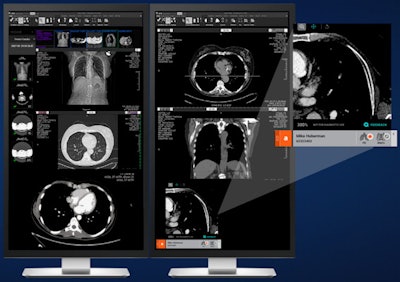

AI Operating System. Image courtesy of Aidoc.The platform facilitates access to Aidoc's portfolio of nine algorithms cleared by the U.S. Food and Drug Administration (FDA) for triage and detection across a range of radiology applications. In addition, it provides access to AI algorithms from companies such as Icometrix, Imbio, Riverain Technologies, ScreenPoint Medical, and Subtle Medical.

AI-based image analysis is used to match the most compatible algorithm with the relevant scan. Furthermore, AI OS can also help to improve communication between caregivers in a health network by providing automated alerts and relevant information for radiologists and other physicians to review, Aidoc said.